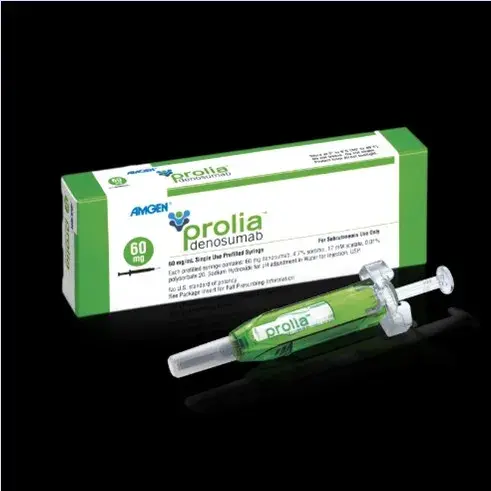

Nefrodica: Denosumabe para hipercalcemia refratária

Nefrodica: Denosumabe para hipercalcemia refratáriaO manejo de um paciente com hipercalcemia nem sempre é fácil, alguns pacientes permanecem refratários mesmo após bifosfonatos. Olha essa dica!

Valkercyo Feitosa